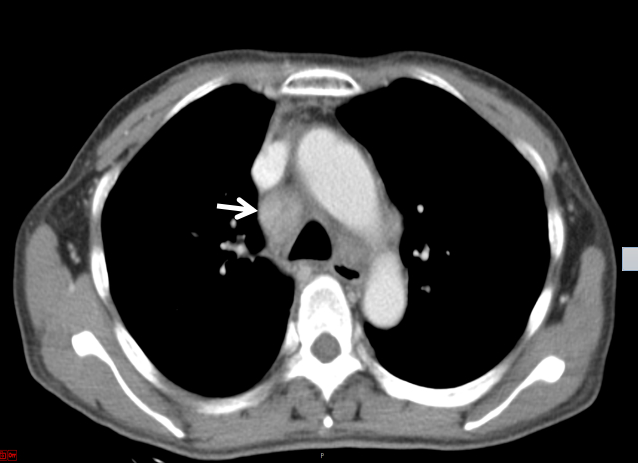

经过上述激素联合免疫抑制剂方案治疗,患者病情无改善,再次出现“发热、咳嗽”加重而就诊于当地医院,考虑肺部感染予泰能及莫西沙星静滴治疗11 d,效果欠佳并加重,鼻导管吸氧下动脉血氧饱和度仅及92%左右,故于2020-01-17转入本院ICU二科进一步诊治。入室时神志清晰,检查合作,浅表淋巴结未触及,腹软,上腹压痛。入室检查:血常规WBC 6.09×109,RBC 3.94×1012,Hb 107 g/L, PLT 33×109。总蛋白51.4 g/L,白蛋白24.16 g/L,总胆红素43 g/L,丙氨酸氨基转移酶339 U/L,门冬氨酸氨基转移酶191 U/L,肌酐34.87 umol/L,胆碱酯酶1346 U/L,降钙素原3.28 ng/mL,C反应蛋白193.5 mg/L,免疫指标阴性。D-DII 18 240 ng/mL,PT 17.1 s,APTT 42.8 s,FIB 5.08 g/L。CD4/CD8 > 1.25∶1。胸部CT示双肺间质广泛增厚并见多发斑片影,双肺肺门及纵隔见增大淋巴结,较图 2中影像增大、部分融合,见图 3。

| 图 3 2020-01-18 CT检查影像示纵膈的改变 |